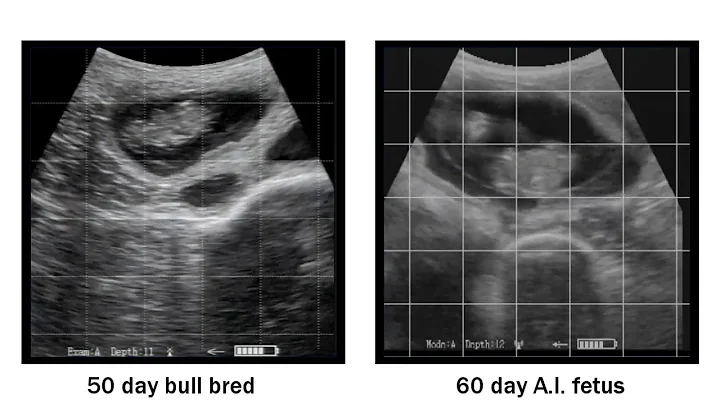

Cow Pregnancy Diagnosed With Ultrasound Technology

Watch a veterinarian diagnose a pregnant cow at 59 days using portable ultrasound technology. For veterinary animal surgical ...